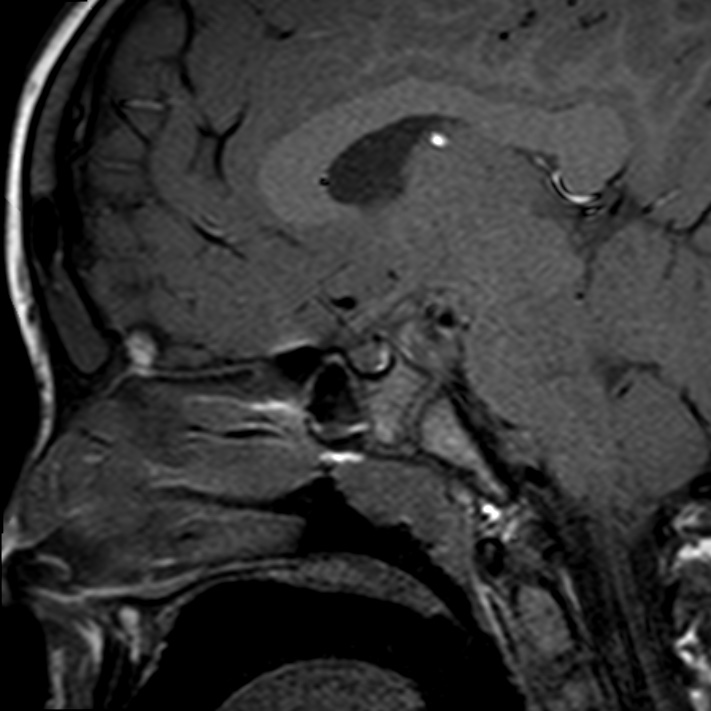

Caso neurorradiología

Paciente de 60 años con cuadro de 1 semana de evolución consistente en tropiezos frecuentes y alteración en la movilidad del miembro

inferior derecho. No refiere

cefalea u otros síntomas asociados, no pérdida de peso, no náuseas o emesis, no

sudoración nocturna. Antecedentes de hipertensión arterial y diabetes.

Resonancia magnética